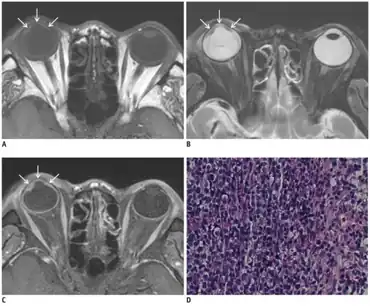

a-c)Posttransplantation intraocular lymphoma- MR images showing smooth, undulating soft-tissue lesion in iris and anterior chamber d)photomicrograph consistent with diffuse large B-cell lymphoma